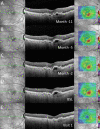

Methods: Patients with recalcitrant nAMD were switched to brolucizumab therapy. Functional and structural parameters 4 weeks after first brolucizumab injection were evaluated including best-corrected visual acuity (BCVA (logMAR)), foveal centre point (FCP (µm)), central subfield retinal thickness (CSRT (µm)) and macular volume (mm³).

Results: Sixty-three eyes of 57 patients with nAMD (52.6% females) with a mean (±SD) age of 79.5±6.7 years were included. Mean change of BCVA was 0.03±0.14 logMAR (p=0.115). Significant reductions were recorded for FCP with a mean (±SD) change of -66.81±72.63 µm, -66.76±60.71 µm for CSRT and -0.27±0.24 mm³ for macular volume (all p<0.001). Intraocular inflammation was observed in seven eyes of seven patients, including one case of retinal vasculitis.